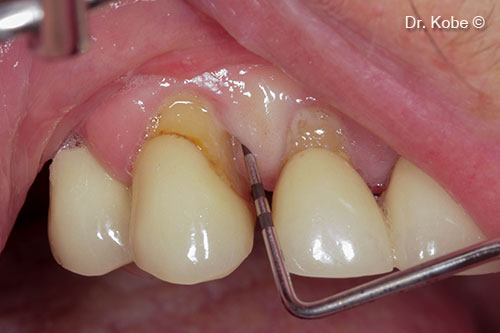

Root scaling and debridement

Root surface cleaned